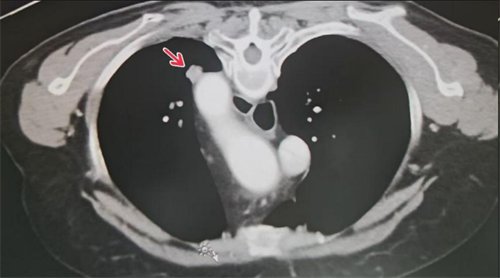

肺转移瘤邻近大血管

家住湖南省岳阳市60岁的李爱霞(化名)2年前确诊为肺癌并双肺转移,口服靶向药及接受放疗后病情控制稳定。今年7月,李爱霞复查发现肺转移瘤增大,而且由于病灶紧贴大血管,手术难度和风险很大。最终,维多利亚老品牌76696vic(南华大学附属长沙中心医院)肿瘤科李岳勇团队凭借丰富的经验,成功为其实施肺转移瘤微波消融术,术后李爱霞恢复良好,顺利出院。这一技术为高危位置的肿瘤患者提供了新的生机。